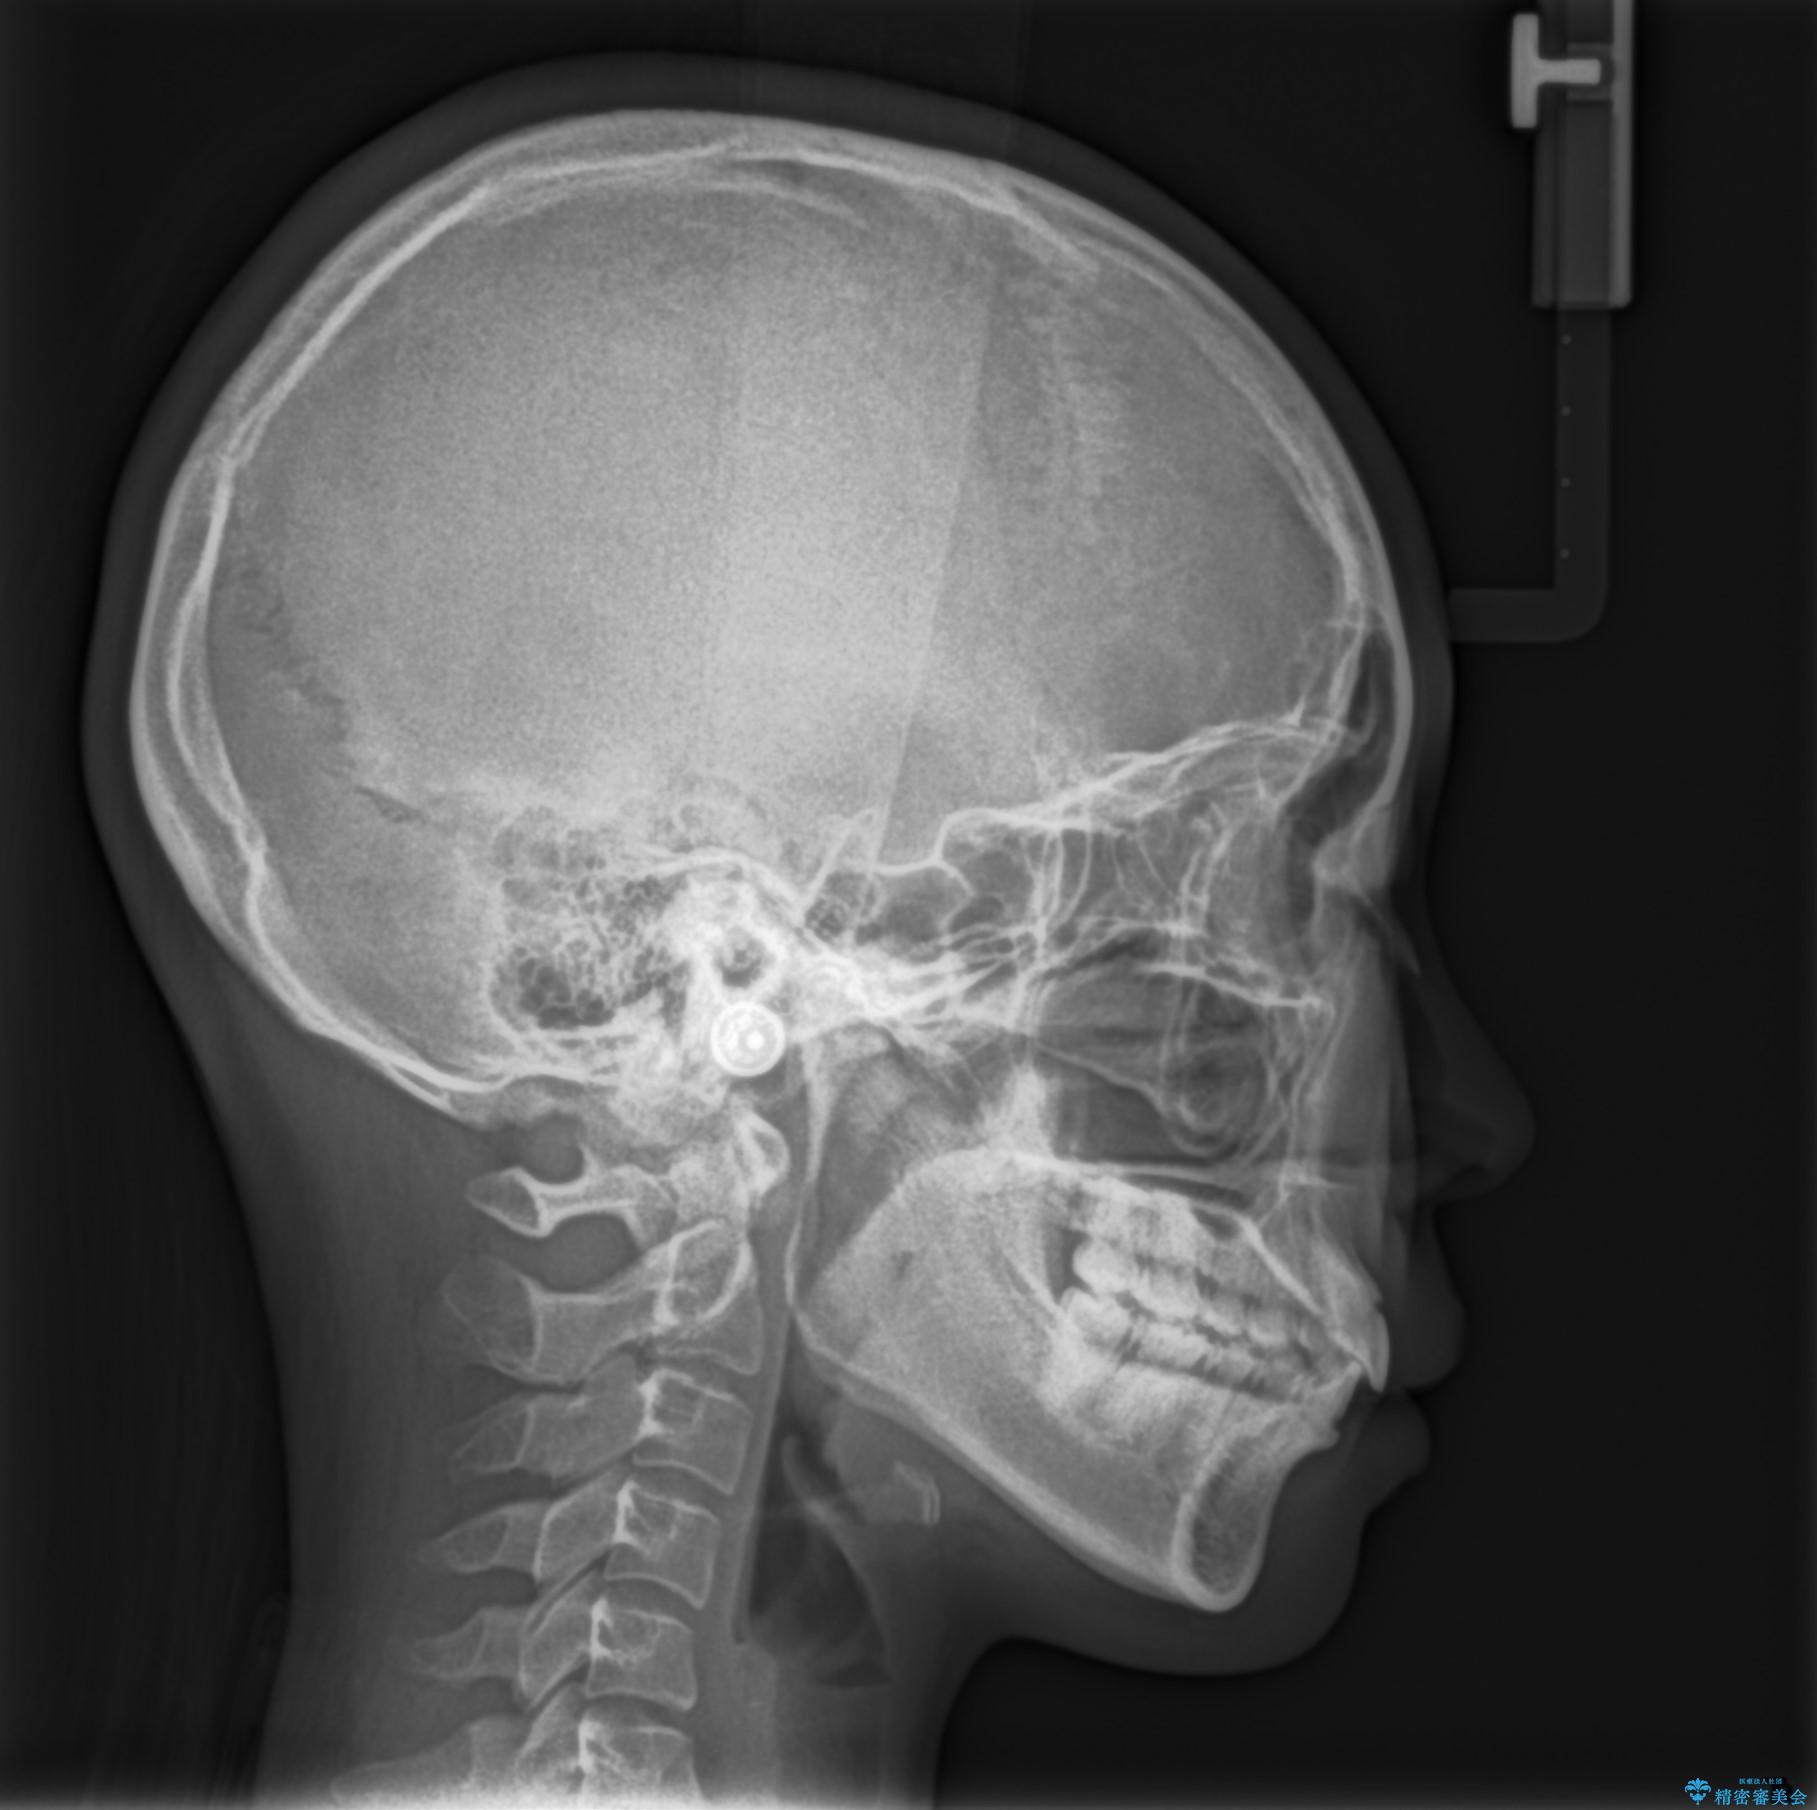

- 前歯の隙間を閉じたいと矯正カウンセリングに来られた患者様です。

マウスピース矯正(インビザライン)を行い短期間で治療が完了しました。